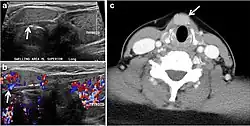

Fig. 4. A 45-year-old male patient presented with anterior mediastinal metastatic PTC lesions and occult primary on imaging. Histopathology examination of the resected thyroid gland revealed micro-foci of PTC; the largest, in the isthmus, measured 4 mm. a transverse greyscale ultrasound of the thyroid demonstrates homogeneous gland with normal echogenicity and size. No focal lesion or micro-calcifications. b Non-enhanced CT scan obtained as part of PET/CT examination shows a heterogeneous, large, relatively dense anterior mediastinal mass (white arrow) with peripheral calcification (arrowheads). Thyroid gland has normal CT appearance with no abnormal FDG uptake (not shown).[1] -

Fig. 7. A 51-year-old female patient post total thyroidectomy for PTC with elevated thyroglobulin measurement. an Axial non-enhanced CT scan of the neck at the level of the thyroid bed demonstrates a well-defined, rounded, homogenously dense soft tissue situated between the trachea and left internal jugular vein (white arrow). b Transverse ultrasound image of the neck demonstrates a well-defined, homogeneous, hypoechoic soft tissue nodule measuring 6 mm (white arrow) with no detected micro-calcifications. Biopsy showed a predominantly residual normal thyroid tissue with micro-foci of PTC.[1] -

Fig. 8. A 48-year-old male patient post total thyroidectomy with PTC recurrence. a Transverse greyscale ultrasound of the neck demonstrates a left thyroid bed heterogeneous, predominantly hypoechoic irregular lesion with calcifications (white arrow). b A spot image of iodine 123 total body scan of the neck demonstrate a focus of abnormal radiotracer uptake at the left thyroid bed (Black arrows) between the annotated markers. c Enhanced axial CT scan of the neck demonstrates an enhancing large left thyroid bed mass (white arrow) with no calcifications. The lesion exerts a mass effect on the oesophagus (black arrow) and is inseparable from the trachea.[1] -